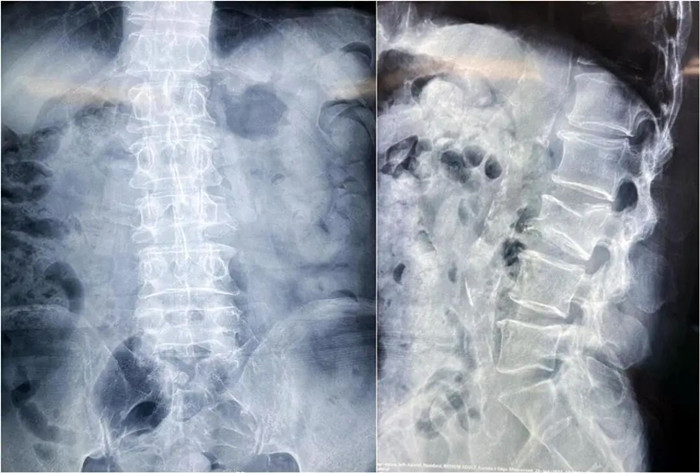

患者情況:腰椎L3壓縮性骨折

南京醫(yī)科大學(xué)第二附屬醫(yī)院骨科副主任醫(yī)師王伯堯帶領(lǐng)團(tuán)隊(duì)成功完成經(jīng)皮椎體球囊擴(kuò)張成形術(shù)(PKP)。該患者為腰椎陳舊性壓縮性骨折,腰部疼痛難忍,活動(dòng)受限,生活受到影響。王醫(yī)生借助普愛醫(yī)療大平板C臂機(jī)高清的圖像及靈活的擺位,快速定位椎弓根位置,確定進(jìn)針點(diǎn),使得手術(shù)得以更加高效和準(zhǔn)確地完成。

患者術(shù)前影像